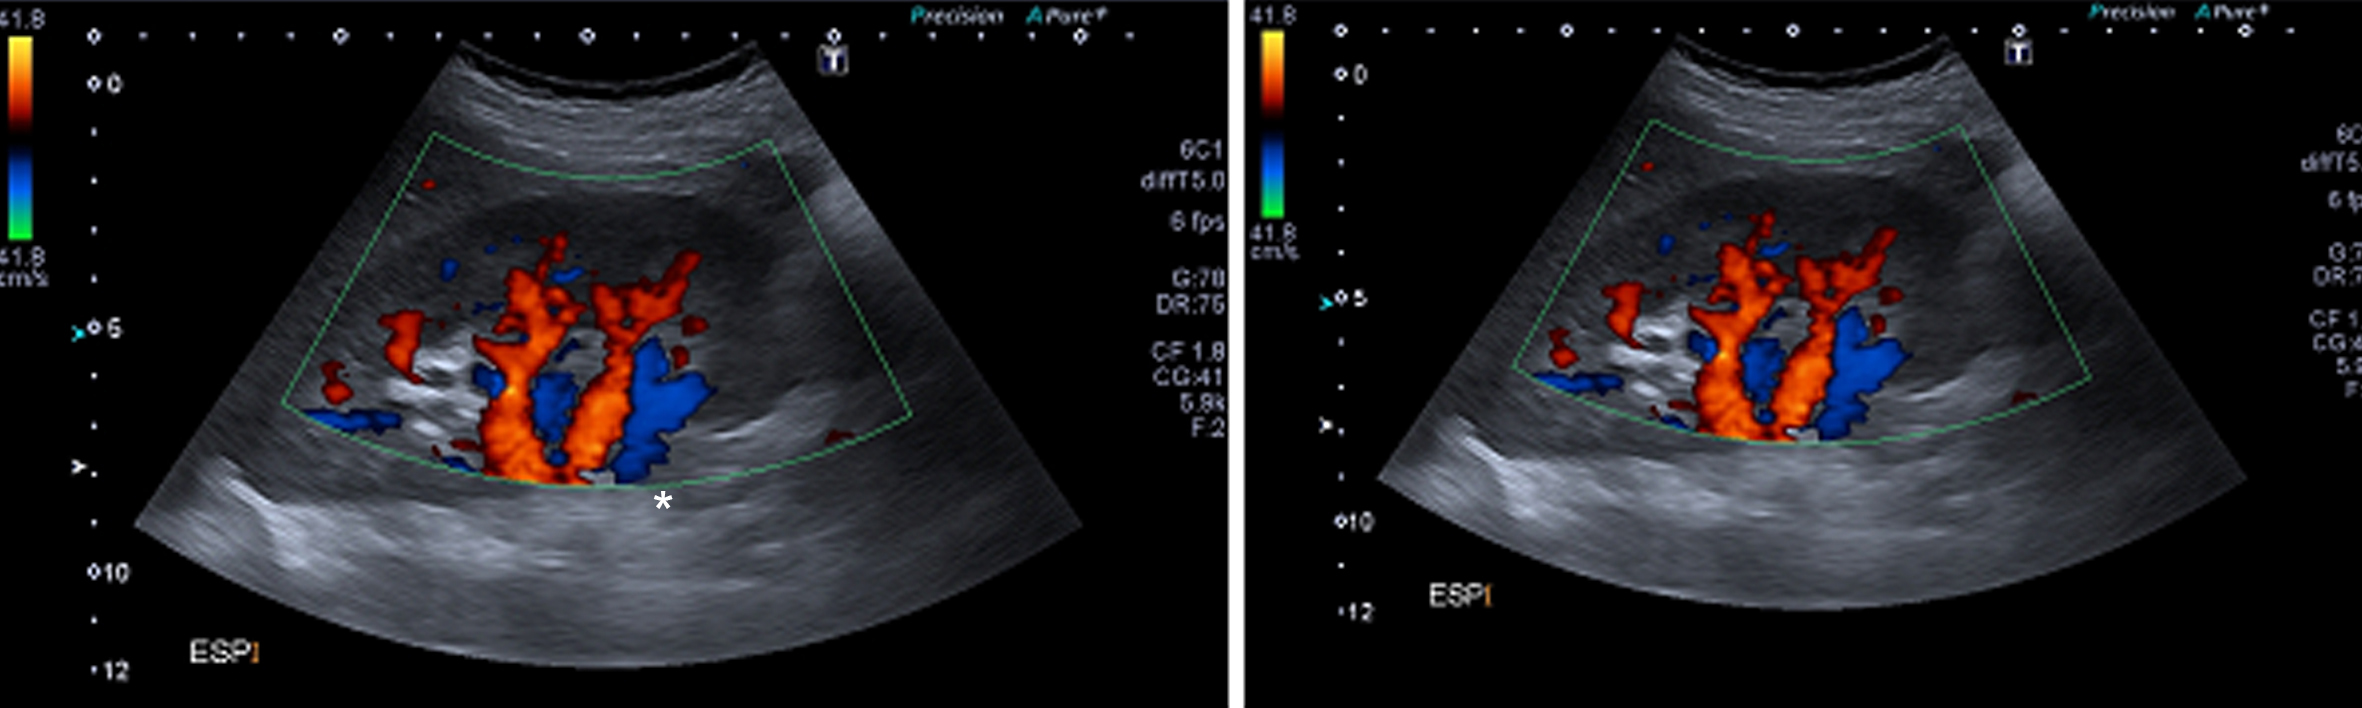

Figura 4

Ecografía Doppler, Cortes longitudinales. En espiración (izquierda) y en inspiración (derecha). (RD) Riñón derecho.

Figura 5

Ecografía Doppler En espiración (izquierda) y en inspiración (derecha). (flecha negra) Arteria renal derecha.

Se comprueba una aorta abdominal ectásica en toda su extensión, con velocidades sisto-diastólicas habituales (velocidad picosistólica de 70 cm/seg.). Ambos riñones son de forma y tamaño habitual, con parénquima de espesor y ecogenicidad normal y buena diferenciación córtico-medular bilateralmente. No se ven alteraciones de las cavidades excretoras. Se realiza estudio dinámico de las arterias renales durante el ciclo respiratorio el cual demuestra que durante la inspiración el sector proximal de la arteria renal derecha se “verticaliza”, quedando paralela a la aorta abdominal, (Fig. 5), comprobándose además aumento de las velocidades sisto-diastólicas en este sector de la arteria, con velocidades picosistólicas (VPS) de 385 cm/seg en inspiración, comportándose desde el punto de vista hemodinámico como una estenosis significativa.

En espiración la arteria tiene un trayecto horizontal y velocidades de flujo normales (VPS de 122 cm/seg) (Fig. 5), siendo la vascularización intrarrenal de distribución habitual y con patrones de flujo normales. (Fig. 4)